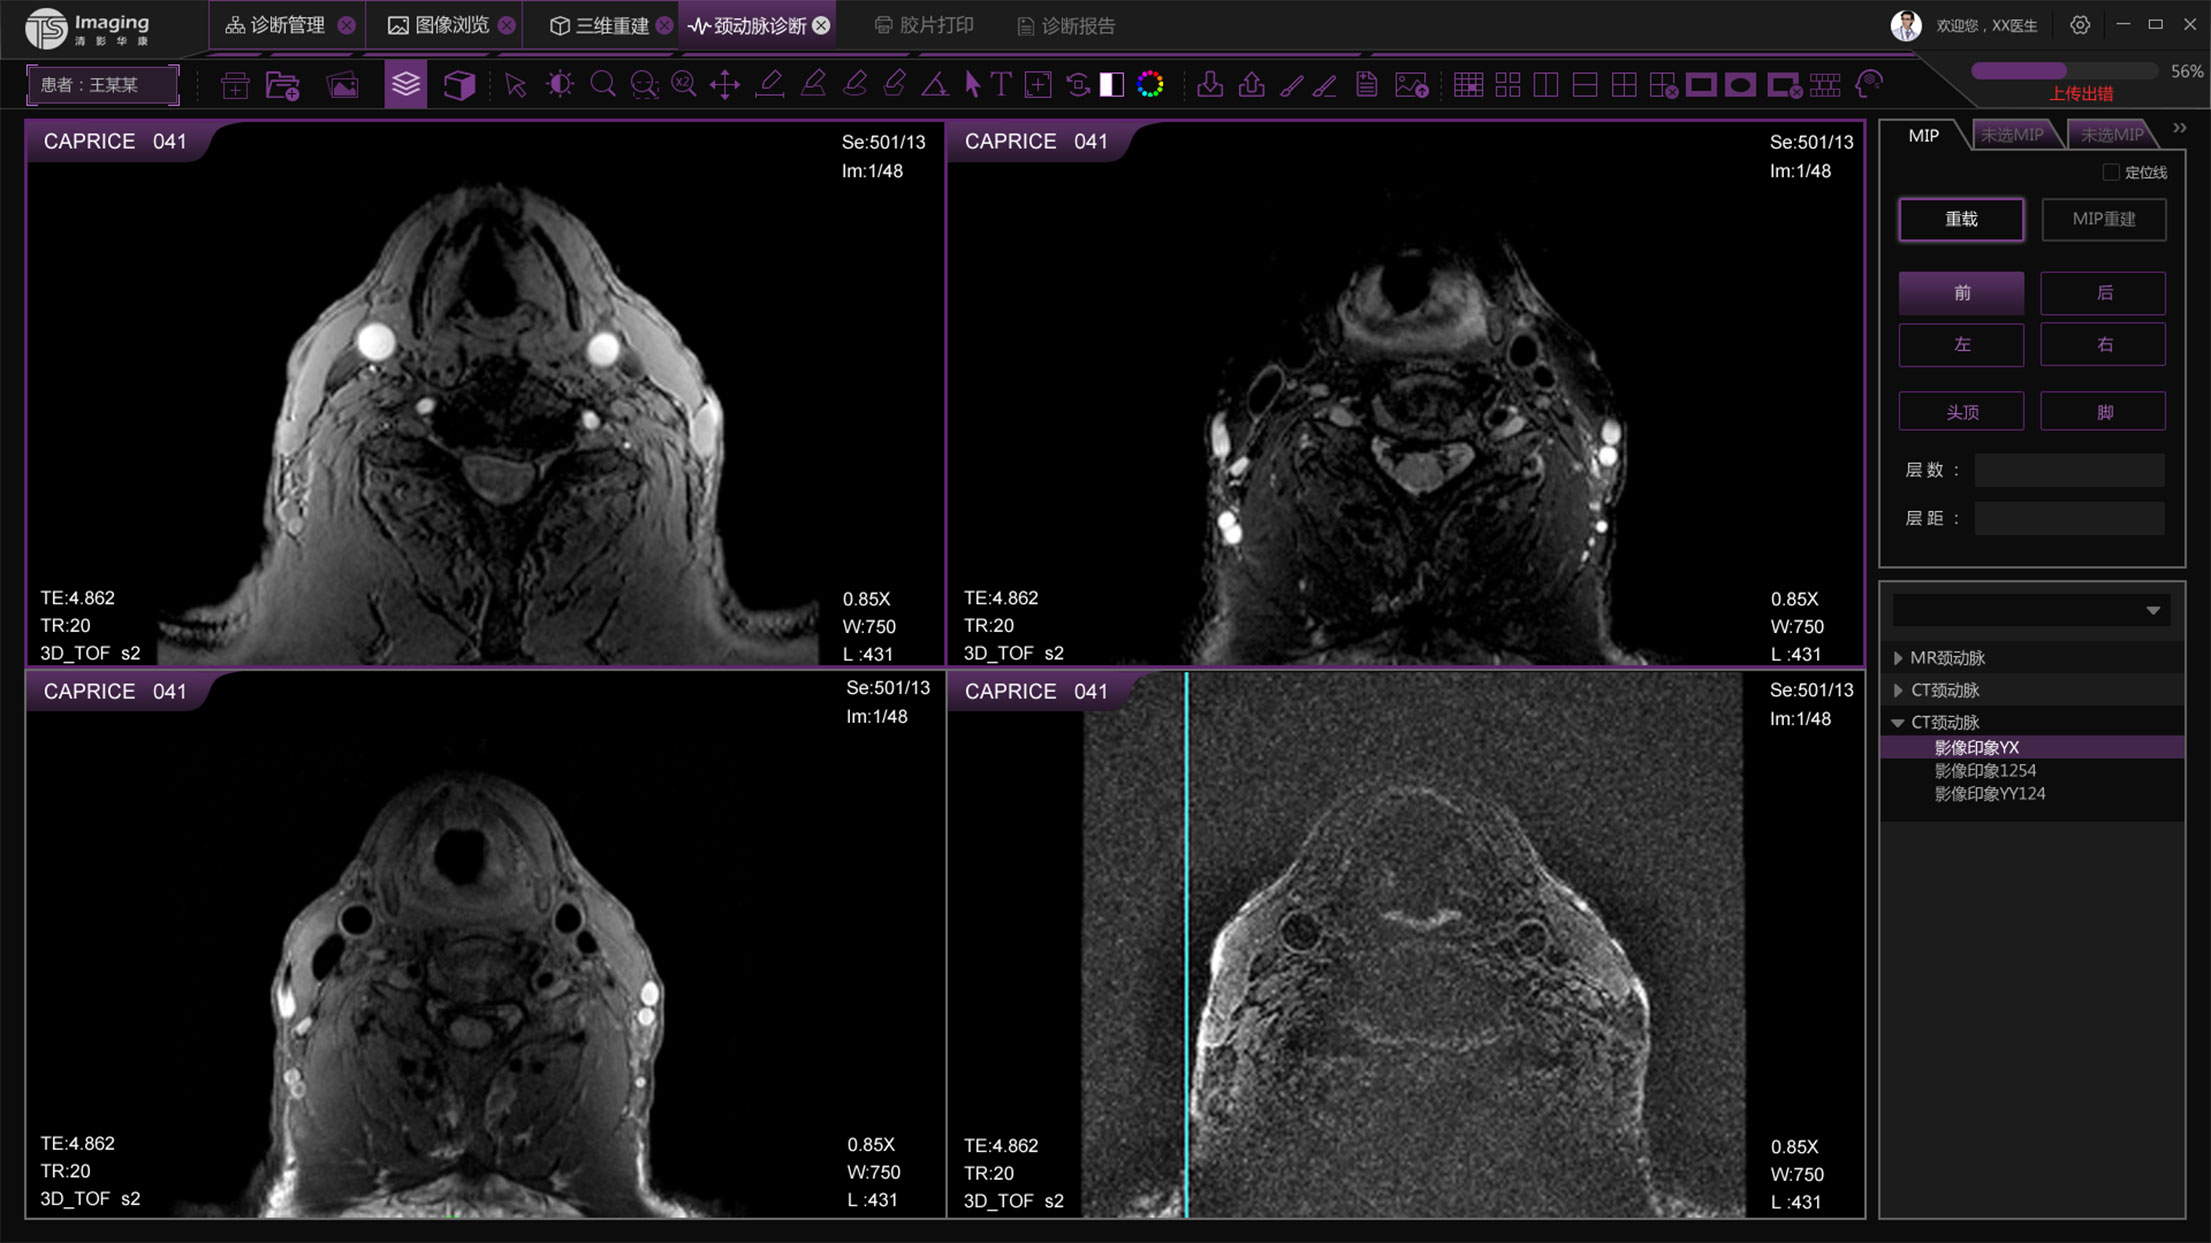

頸動(dòng)脈診斷頁(yè)面

頸動(dòng)脈診斷頁(yè)面整體布局和三維重建比較相似,最大的區(qū)別是右側(cè)的操作區(qū)域,血管分析都為按鍵操作,通過(guò)間隔的大小分成三部分。單層切片除了按鍵還有下拉菜單的操作。